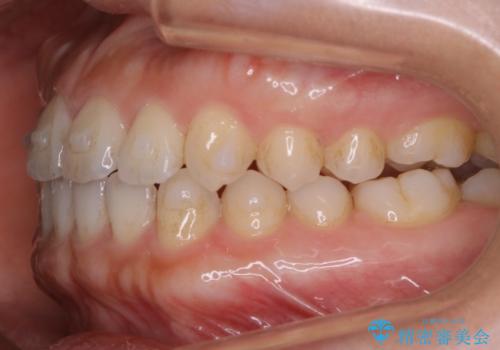

- 矯正治療を主訴にご来院されました。

すきっ歯と噛み合わせの治療をしたいとのことで、インビザラインを用いて矯正治療を行うこととなりました。

すきっ歯の場合、ガタつきを治したりするのに必要なスペースが最初から空いているため、そのスペースを利用して比較的短期間で効率よく治療を進めることが可能となります。

初診時の写真では一見噛み合わせには問題がないように見えても、実際に精密な検査を行うと改善すべき点が見つかる場合も多くあります。